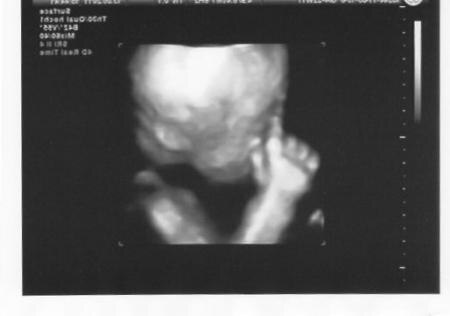

und noch eins.... hihi

Bild zu